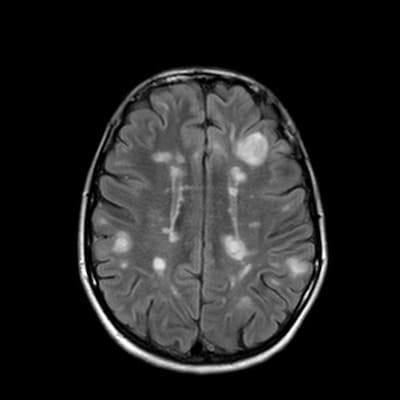

- Brain imaging studies such as CT or MRI

Advanced neuroimaging techniques like diffusion-weighted MRI can help assess the extent of brain damage and potentially predict outcomes. Additionally, biomarkers in blood or cerebrospinal fluid may provide valuable prognostic information.